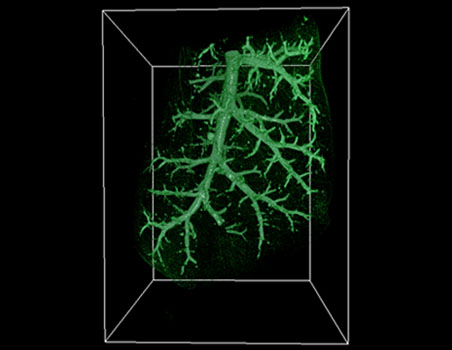

Mapping microscopic worlds

Maurice Wilkins Centre researchers have used unique microscopic imaging techniques to peer into the three-dimensional structure of blood vessel networks – and new computational tec

Exquisite networks (2011)

Innovative technology developed to study the heart has been adapted for a unique study of the immune system – and will now be applied to cancer, through cross-disciplinary links fo

Lighting up lymph nodes (2009)

Maurice Wilkins Centre researchers have made exciting new discoveries about how human lymph nodes work.